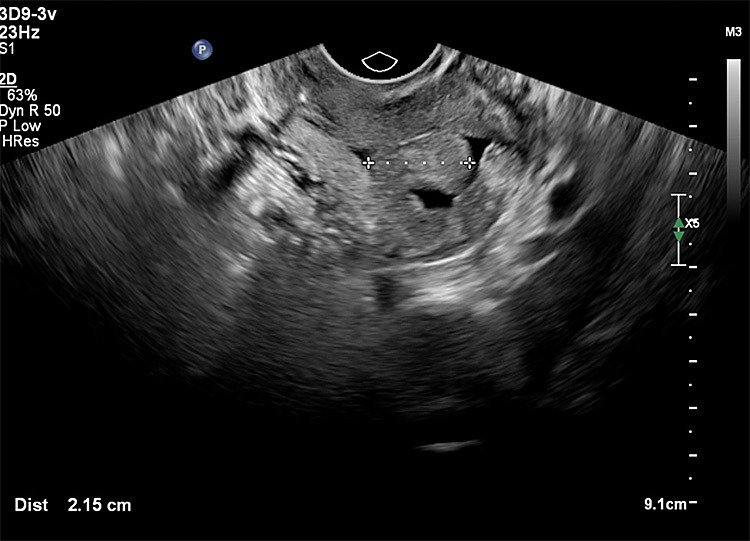

Οι παρακάτω τέσσερις εικόνες δείχνουν:

Δυο υπερηχογραφικές μελέτες πολύποδα και πώς διερευνάμε το ενδομήτριο ( 1 και 2 )

Το ενδοκολπικό υπερηχογράφημα είναι μια κοινή και αποτελεσματική μέθοδος για την ανίχνευση ενδομητρικών πολυπόδων. Περιλαμβάνει τη χρήση ενός ηχοβολέα που εισάγεται στον κόλπο για να παρέχει λεπτομερείς εικόνες της μήτρας. Αυτή η μέθοδος είναι ιδιαίτερα χρήσιμη για την αναγνώριση πολυπόδων σε μετεμμηνοπαυσιακές γυναίκες, οι οποίες συχνά δεν παρουσιάζουν συμπτώματα.

Η υδρο-υπερηχογραφία, είναι μια προχωρημένης τεχνολογίας τεχνική υπερηχογράφησης όπου εγχέεται φυσιολογικός ορός διαμέσου τραχηλικού καθετήρα, στην ενδομητρική κοιλότητα για να βελτιώσει την απεικόνιση. Επειδή το υγρό φαίνεται μαύρο στο υπέρηχο οι επιφάνειες των εσωτερικών ανωμαλιών και πολυπόδων διαχωρίζονται και μπορούν να μετρηθούν αλλά και να χαρτογραφηθούν με μεγαλύτερη ευκρίνεια. Αυτή η μέθοδος βελτιώνει την εκτίμηση της ενδομητρικής κοιλότητας, καθιστώντας ευκολότερη την ανίχνευση και τη μέτρηση των πολυπόδων με ακρίβεια. Η υδρο-υπερηχογραφία είναι ιδιαίτερα ευεργετική για τη διάκριση των πολυπόδων από άλλες ενδομήτριες παθολογίες, παρέχοντας μια καθαρότερη και πιο λεπτομερή αξιολόγηση σε σύγκριση με το απλό δισδιάστατο γυναικολογικό υπερηχογράφημα.